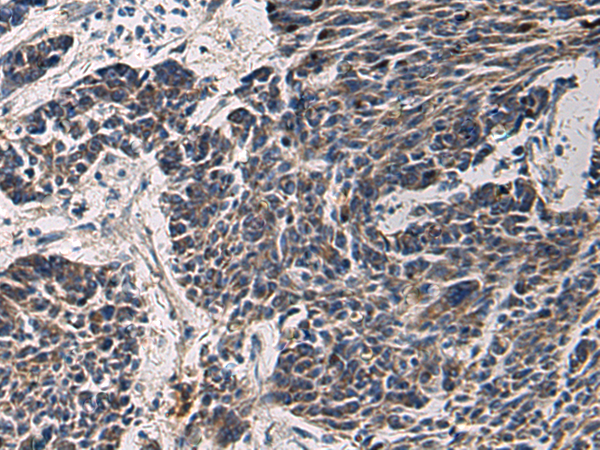

IHC positive control: |

Human esophagus cancer and Human colorectal cancer |

IHC Recommend dilution: |

50-200 |